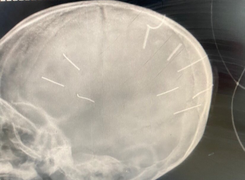

(VTC News) - Kết quả phim chụp X-quang cho thấy, bé Đ.N.A., 3 tuổi, ở Canh Nậu, Thạch Thất, Hà Nội có đinh trong sọ, tiên lượng tử vong cao.